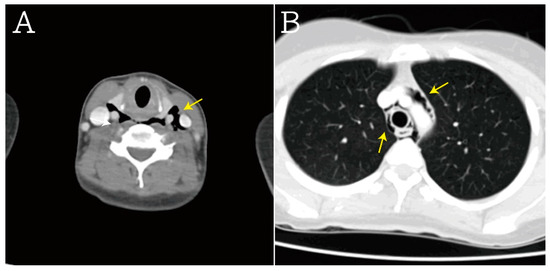

2. Case Presentation